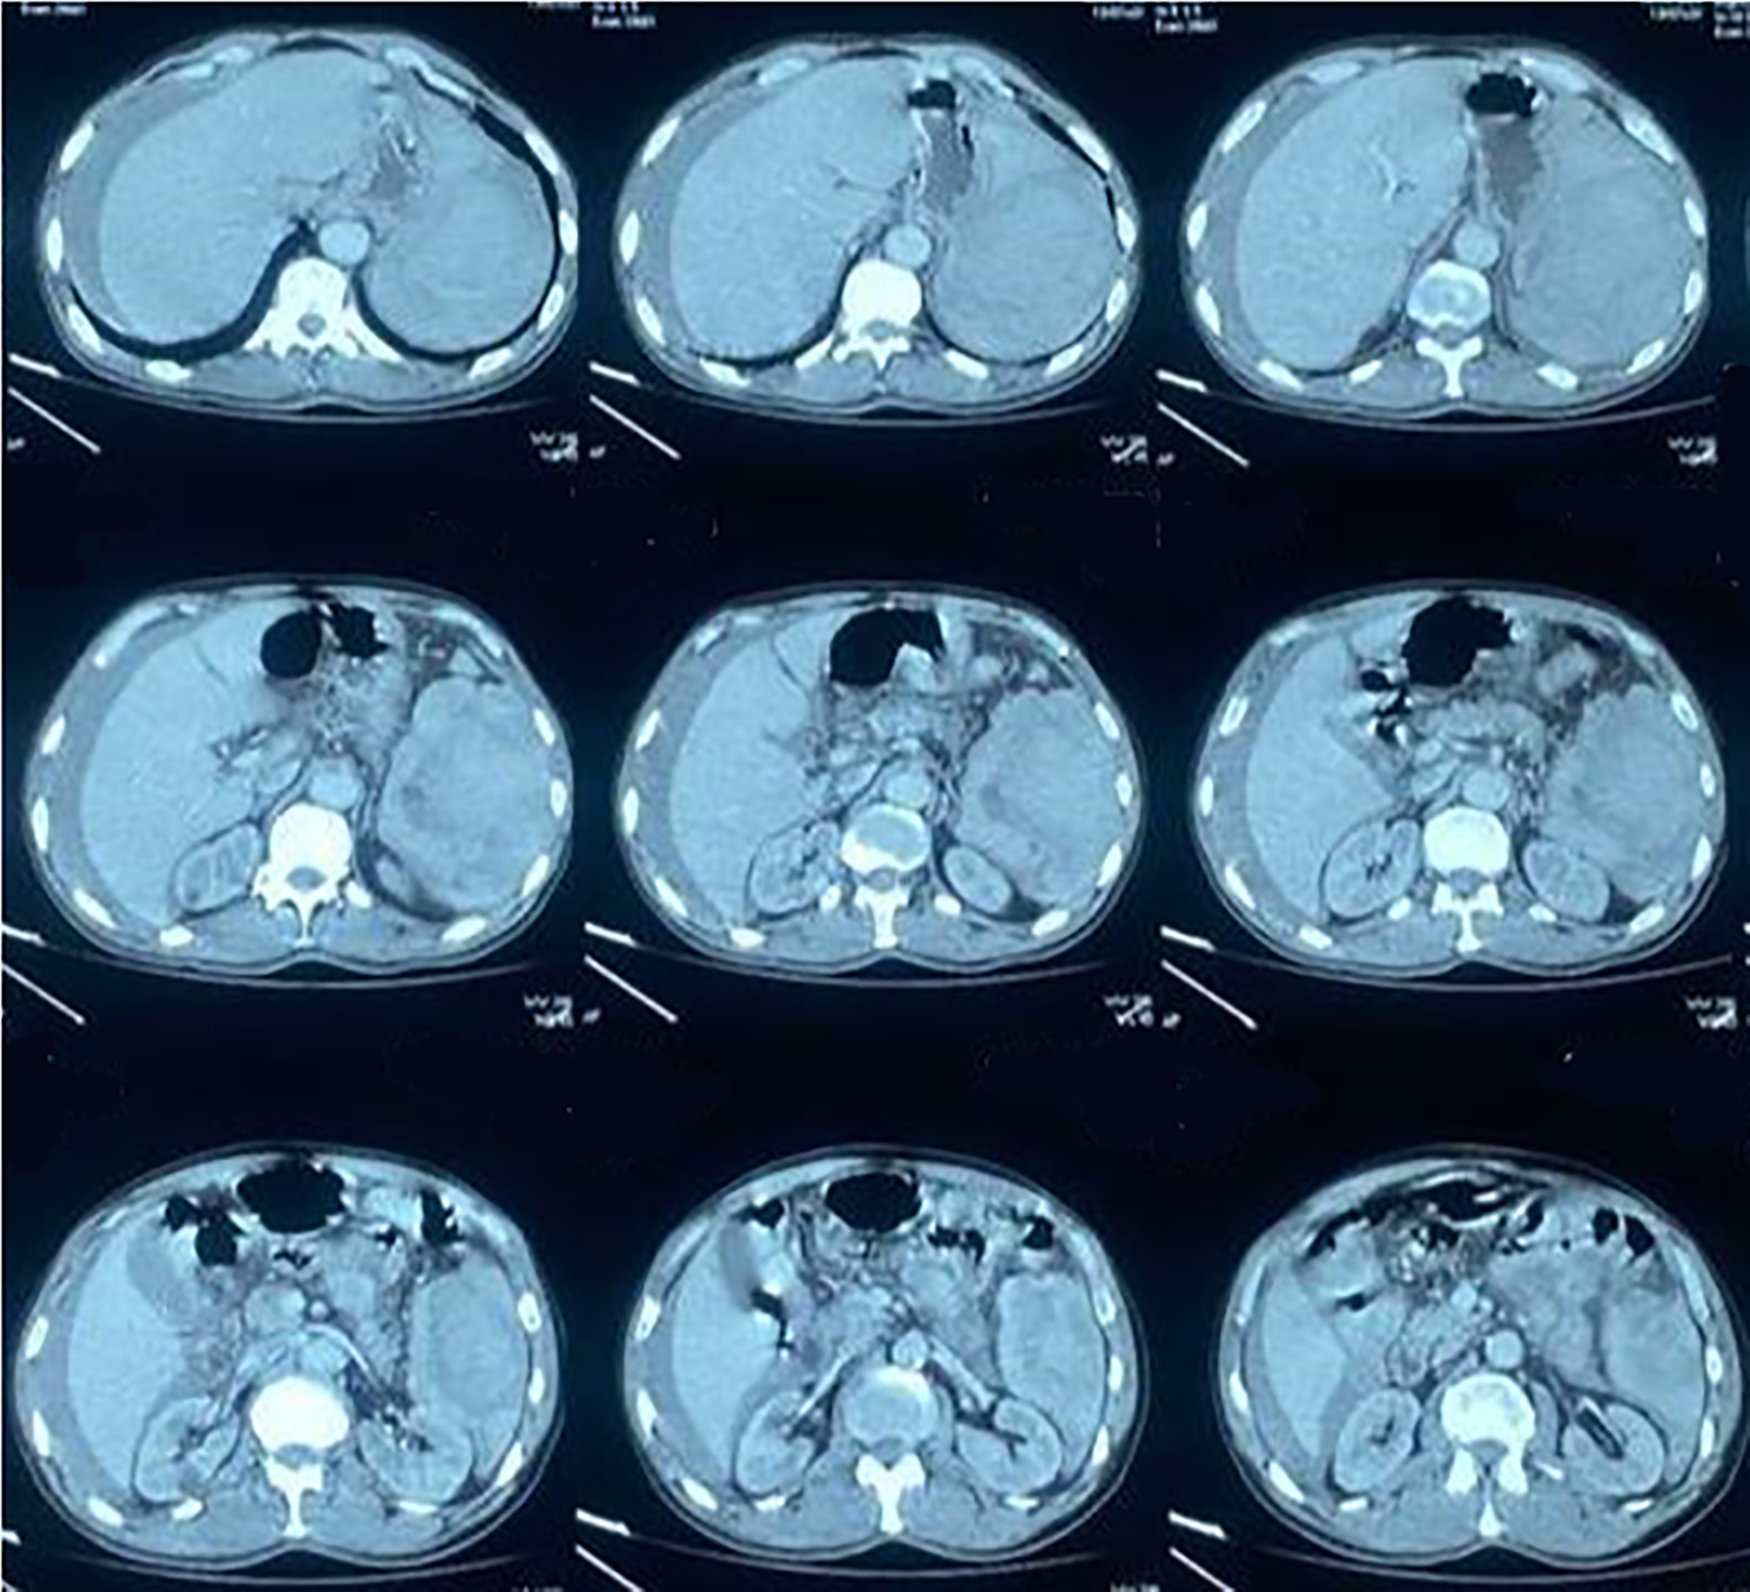

The patient had an abdominal ultrasound, which showed the presence of a heterogeneous echogenic formation in the left hypochondrium with regular contours. It was poorly limited and non-vascularized on Doppler and was of adrenal or splenic origin. An abdominal CT scan (Fig. 1) showed a splenic hematoma associated with a dense intraperitoneal effusion of moderate to large volume and a ruptured splenic hematoma with uncomplicated vesicular lithiasis.

Fig. 1. Abdominal CT showing the ruptured spleen with intraperitoneal effusion.